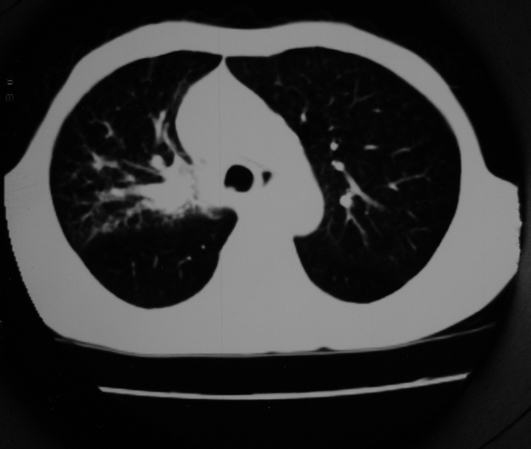

以下是引用同在2007-1-27 14:13:00的发言:[br]支持右侧中央型肺癌伴阻塞性病变.

以下是引用zjzjr在2007-1-27 16:56:00的发言:[br]支持右肺中心型肺癌伴阻塞性肺炎.